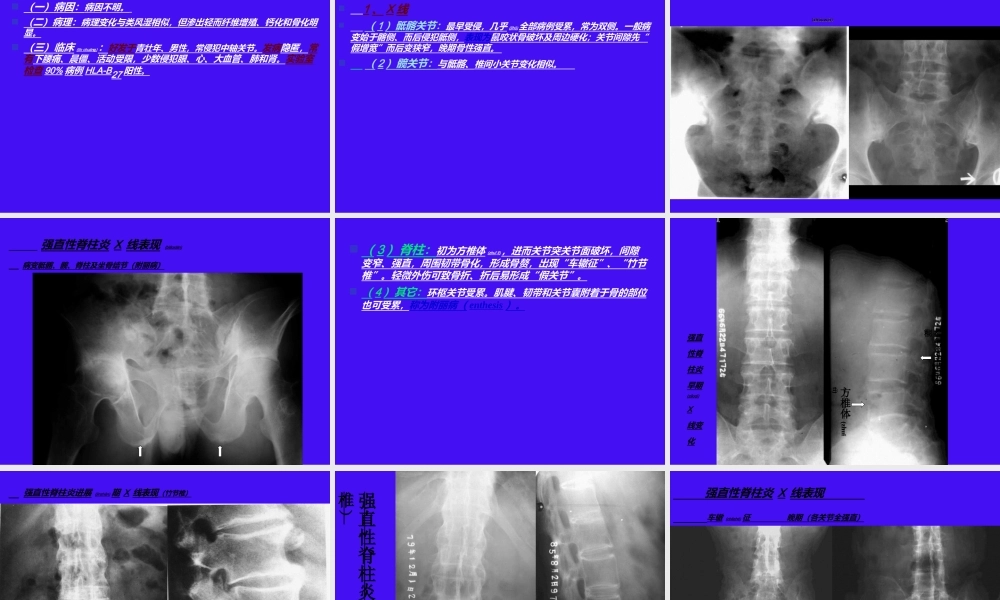

骨、关节及软组织系统(xìtǒng)影像诊断学(医学影像专业五年制)骨、关节及软组织系统影像诊断学第六节慢性(mànxìng)关节病一、类风湿性关节炎二、强直性脊柱炎三、退行性骨关节病(补充颈椎病)第六节慢性关节病慢性关节病的特点是发病慢,病程(bìngchéng)长,全身关节受损。一、类风湿性关节炎(Rheumatoidarthritis)(一)病因:病因不明。(二)病理:关节滑膜非特异性慢性炎症。表现为滑膜肿胀、渗出、血管翳,骨、关节软骨破坏,关节面下囊性变,最终关节纤维性强直等。(三)临床:●多见于中、青年(qīngnián)女性,常两侧腕、手、足小关节受累。●早期有低热、肌肉酸痛、消瘦,进而关节软组织梭形肿胀、疼痛、僵硬,肌萎缩和半脱位等。●实验室检查血沉快,类风湿因子阳性等。(四)影像学表现1、X线●早期:手足腕关节多发性软组织肿胀、手足肿胀呈梭形,关节间隙先宽后窄,骨端骨质疏松,边缘虫蚀状骨破坏。(zǎoqī)(zǎoqī)●进展期:骨性关节(guānjié)面模糊、中断,骨端小囊状透明区,关节(guānjié)间隙狭窄及骨质疏松加重。●晚期:严重骨破坏,肌肉萎缩,半脱位,最终多发生纤维性关节强直。●其它:①跟骨后下缘增生和破坏,胸水和肺炎等。②因受累关节病程不一,同一患者可见不同病期表现。类风湿性关节炎进展(jìnzhǎn)期X线表现双腕及手关节软组织肿胀,骨质疏松(shūsōnɡ),关节间隙狭窄,关节面边缘破坏,面下囊变类风湿性关节炎晚期(wǎnqī)X线表现类风湿性跟骨炎2、MRI(1)早期:以滑膜炎表现为主,呈长T1、长T2信号。注射Gd-DTPA后、炎性滑膜(huámó)明显强化。(2)进展期:滑膜、关节内软骨、骨性关节面及骨端破坏区的血管翳互相延续,呈长T1、长T2信号。增强见明显强化。类风湿性关节炎MRI表现(biǎoxiàn)手及腕关节冠状面膝关节矢状面T1WI示腕骨(wàngǔ)破坏呈低信号,滑膜增厚、毛糙。T1WI示膝关节骨破坏呈低信号(xìnhào),滑膜增厚、毛糙。T2WI示膝关节骨破坏呈高信号,滑膜增厚、毛糙。(五)诊断、比较影像学及鉴别诊断●临床结合影像表现和类风湿因子阳性可确诊。●早期诊断临床和MRI较好。●鉴别①关节结核。②痛风性关节炎间歇发作(fāzuò),男性多,第一跖趾关节常先受累,有痛风结节和血尿酸高。二、强直性脊柱炎(Ankylosingspondylitis)(一)病因:病因不明。(二)病理:病理变化与类风湿相似,但渗出轻而纤维增殖、钙...